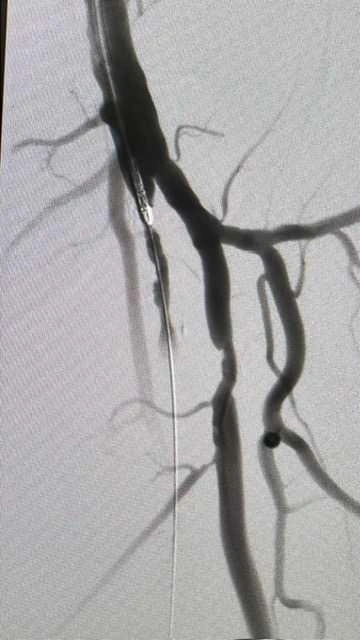

«Система JetStream — это современная технология для лечения критической ишемии и нарушения артериального питания нижних конечностей. Через небольшой прокол в сосуд вводится миниатюрный инструмент с вращающимися лезвиями, совершающими до 40 000 оборотов в минуту. Он аккуратно срезает атеросклеротические бляшки, а встроенная система аспирации сразу же удаляет их из организма», — пояснил Михаил Воронин.

Главное преимущество метода в том, что он обеспечивает долговременное восстановление кровотока — на срок до 5 лет и более. В отличие от ротационной абляции, которая применяется в сердечных артериях и измельчает бляшки, JetStream физически удаляет их из сосудов, что снижает риск повторного сужения.